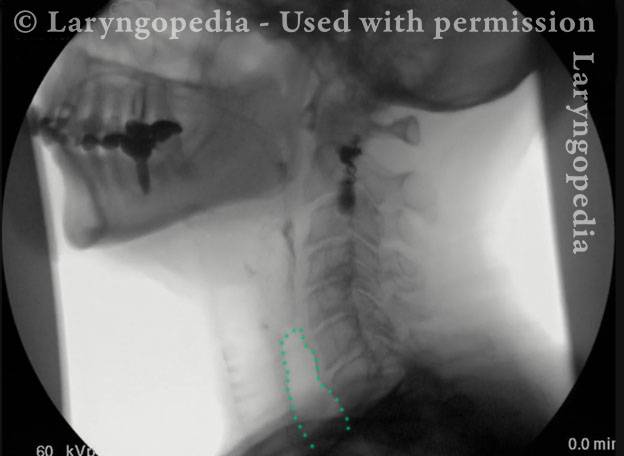

This visual series depicts a hallmark feature of R-CPD: marked dilation of the upper esophagus filled with swallowed and retained air. Normally, this air would be burped out, but in persons with R-CPD, it cannot be expelled.

The retained air can push upward, creating a sense of pressure and a distinct gagging or “throat nausea” sensation. It also explains a striking procedural observation: during office upper esophagoscopy, air insufflation is unnecessary, because the patient’s esophagus is already dilated by trapped air, allowing visualization of its walls.

X-Ray of Dilating Air (1 of 4)